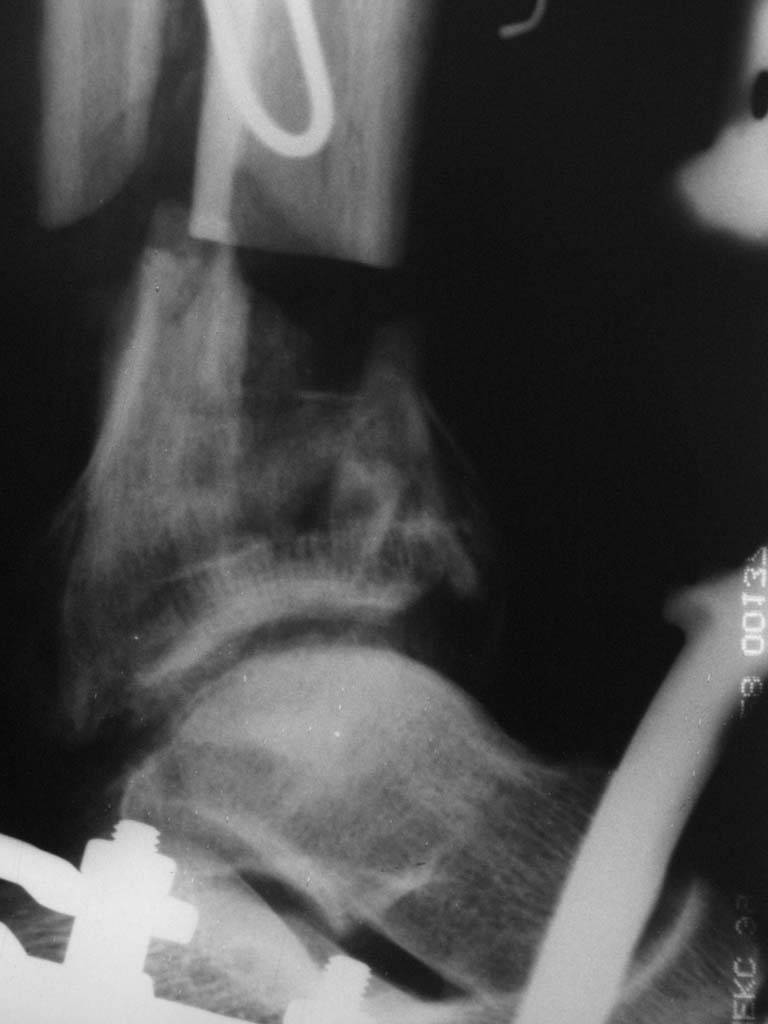

|  |  |  |  status localis на 14.11.08 (В ране визуализируется сухожилие.) | Больной А, 40 лет, находится в клинике с 15.10.08 с диагнозом: Сочетанная травма. Ушиб головного мозга лёгкой степени тяжести. Компрессионные переломы тел 12 грудного и 5 поясничного позвонков без неврологических осложнений. Закрытый внутрисуставной многооскольчатый перелом дистальных метаэпифизов обеих костей правой голени со смещением. Открытый внутрисуставной многооскольчатый перелом дистальных метаэпифизов обеих костей левой голени со смещением (см. Р-граммы). Хронический алкоголизм. Доставлен СМП после падения с 5-го этажа (не суицид). При поступлении состояние тяжелое. Глубокое оглушение. Дыхание самостоятельное, адекватное. Гемодинамика стабильная. По внутренней поверхности левой голени, в нижней трети, рвано-ушибленная рана 10-6 см, из раны выстоит проксимальный отломок большеберцовой кости, рана обильно загрязнена землёй. Интенсивная терапия в условиях реанимационного отделения, вытяжение за правую пяточную кость, параартериальная блокада обеих нижних конечностей, гипсовая лонгета на левую нижнюю конечность, ас-повязка на рану. Через 4 часа после поступления оперирован: после неоднократного промывания раны тёплой проточной водой с мылом, антисептиками, при ревизии определяется земля в канале проксимального отломка на глубину 3 см..., отсутствие надкостницы на концах дистального и проксимального отломков на 3 см. Удалено значительное количество мелких костных фрагментов, перемешанных с землёй, выполнена ПХО раны, резекция проксимального конца большеберцовой кости на 3,5 см, ЧКДО аппаратом Илизарова. Рана не ушивалась. В последующем перевязки раны с "Левомеколь", через 3 недели с момента травмы в ране определялись грануляции, нежизнеспособный конец дистального отломка. 10.11.08 ВХО раны, резекция дистального отломка на 3 см, перемонтаж аппарата наружной фиксации (см. Р-граммы). Отломки сближены на 2 см (остеотомию малоберцовой не делали). В настоящее время (5 сутки после операции) незначительное количество серозного отделяемого из раны, имеется дефект кости 4 см (см. Р-граммы). В последующем склоняемся к перемонтажу аппарата наружной фиксации, остеотомии малоберцовой кости в области повреждения, сближении отломков. По заживлению раны удлинение левой голени на 4 см. Однако, некоторыми высказывалось мнение о необходимости артродеза. Представляем рентгенограммы левой голени при поступлении, после повторного оперативного лечения и фото st.localis на 14.11.08. Будем очень благодарны за критику, комментарии, пожелания и мнения о дальнейшей тактике лечения.

В случае гладкого заживления раны, при условии положительного решения вопроса с металлом, планируем перемонтаж аппарата Илизарова, дополнительную резекцию дистального отломка, выведение полокости голеностопного сустава в правильное положение (см. боковую Р-грамму), одномоментно остеотомия большеберцовой кости. После восстановления длинны голени, по всей видимости, артродез голеностопного сустава.

Рентгенограммы прилагаются. Фото местного статуса выложу в ближайшее время.